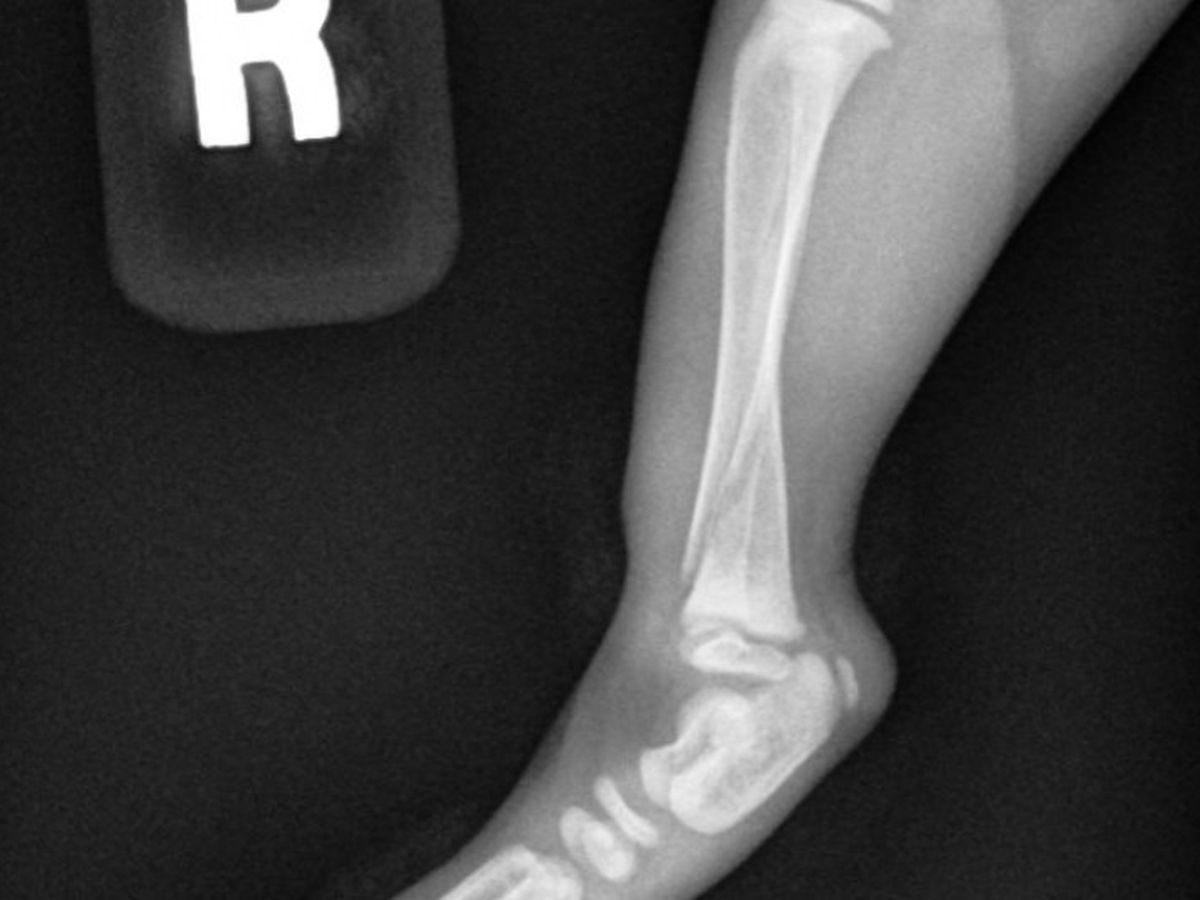

Baby Baily is a kitten we are fostering for Focus on Ferals out of Byron Center, Michigan. On the morning of Sunday, August 20th, we noticed Bailey was limping. We took him to the emergency vet and discovered he had broken his tibia. Fortunately the break isn't significantly displaced, so we're hoping he heals up nicely! Focus on Ferals has taken in quite a few medical cases over this summer and are really running low on funds.